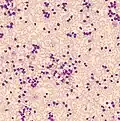

Acute leukemia or acute leukaemia is a family of serious medical conditions relating to an original diagnosis of leukemia. In most cases, these can be classified according to the lineage, myeloid or lymphoid, of the malignant cells that grow uncontrolled, but some are mixed and for those such an assignment is not possible.[1]

Images